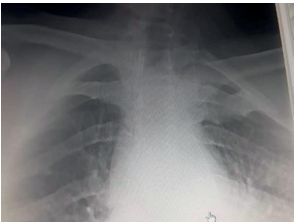

It is was closed by planes until it reacheds the skin, a control x-ray is was performed, where a reduction of the fracture and good positioning of the plate is observed (Figure 3). The patient is was immobilized for 3 weeks with a sling. After 12 weeks later, the Constant score is applied and a score of 85 (excellent) is obtained. Subsequently, at 12 weeks, the hook plate is was removed in a second operation.

Figure 3

Figure 3. Reduction of the fracture and good positioning of the plate.